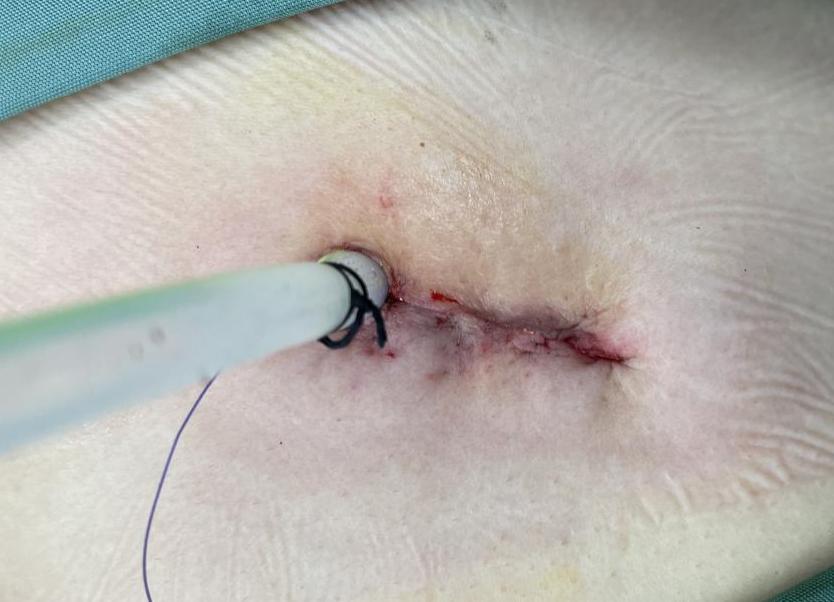

气胸首次发作,无明确肺大泡者,经休息可自行吸收,或行胸穿、胸腔闭式引流排气,解除肺组织压缩;但经保守治疗后16-55%的患者在1年内会复发,而复发再继续保守治疗,此后复发率将高达到80%,对于反复发作或者患有慢阻肺、肺气肿、肺大泡的气胸患者,一定要尽早手术治疗。经过外科手术治疗后,复发率大大降低,是自发性气胸最确切的治疗方式。

根据我们既往经验发现,气胸患者往往都会存在或大或小的肺大泡,再加上近几年胸外科微创技术的发展,临床越来越推荐手术治疗,毕竟单孔胸腔镜手术的切口小、住院时间更短、复发率更低,其优势越来越明显。